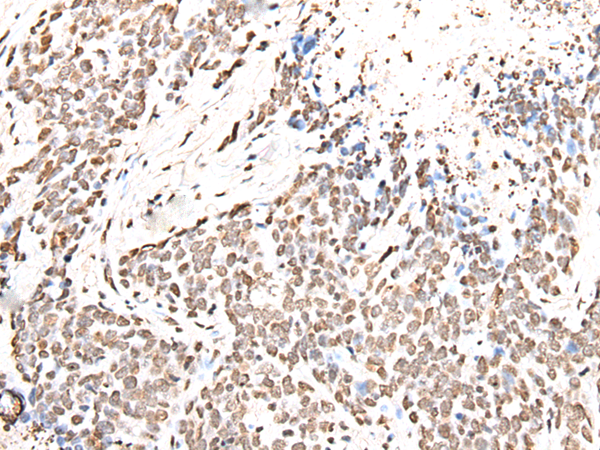

ELISA, IHC

IHC positive control:

Human thyroid cancer and Human tonsil

IHC Recommend dilution:

25-100